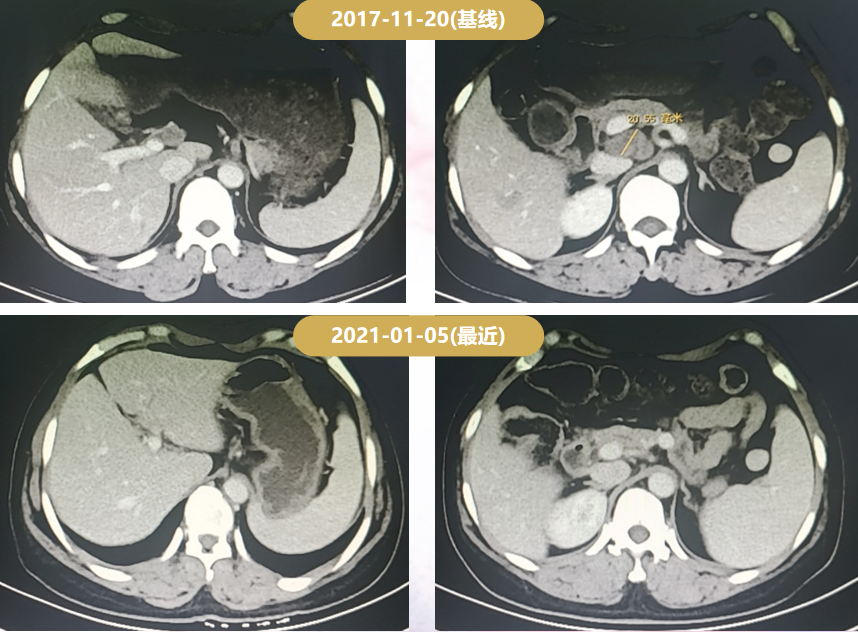

2017-11-20复查增强CT示:腹腔、后腹腔淋巴结肿大,PD出组。

Δ一线治疗期间的CT疗效评价

Δ二线治疗期间的CT疗效评价

患者为绝经前女性,右乳癌术后,肝转移、骨转移、腹腔淋巴结转移,HR-/HER2+。术后仅接受TEC辅助化疗6周期,DFS为39月;2017-03-10至2017-11-20:曲妥珠单抗+多西他赛6周期序贯曲妥珠单抗靶向治疗6周期,最佳疗效PR,PFS为8.3月;2017-12-07至今接受T-DM1二线治疗(3.6 mg/kg q3w IV),PFS>46个月,患者耐受性良好。

对于HER2阳性晚期乳腺癌的二线治疗,EMILIA研究证实,T-DM1可较拉帕替尼+卡培他滨显著延长患者PFS(9.6 vs 6.4个月)和OS(30.9 vs 25.1个月),2021年ESMO更新的EMILIA研究亚洲人群数据显示OS同样获益明显(34.3 vs 22.7个月),且安全性良好(T-DM1的≥3级AE率和停药率均低于LC组)。因此,目前国内外指南均将T-DM1作为HER2阳性晚期乳腺癌的标准二线治疗方案。当前病例印证了EMILIA研究结果,患者在二线治疗中进入BO29919临床研究,并幸运地分配至T-DM1组,从2017-12-07开始治疗至今,PFS已长达46个月,且耐受性良好(仅出现轻度的ALT及AST升高)。